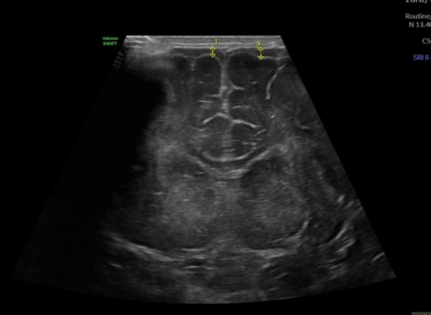

Ecografía Transfontanelar

Se realiza en bebés a través de la fontanela (mollera) para evaluar el cerebro. Ayuda a detectar hemorragias, hidrocefalia o alteraciones neurológicas en recién nacidos.